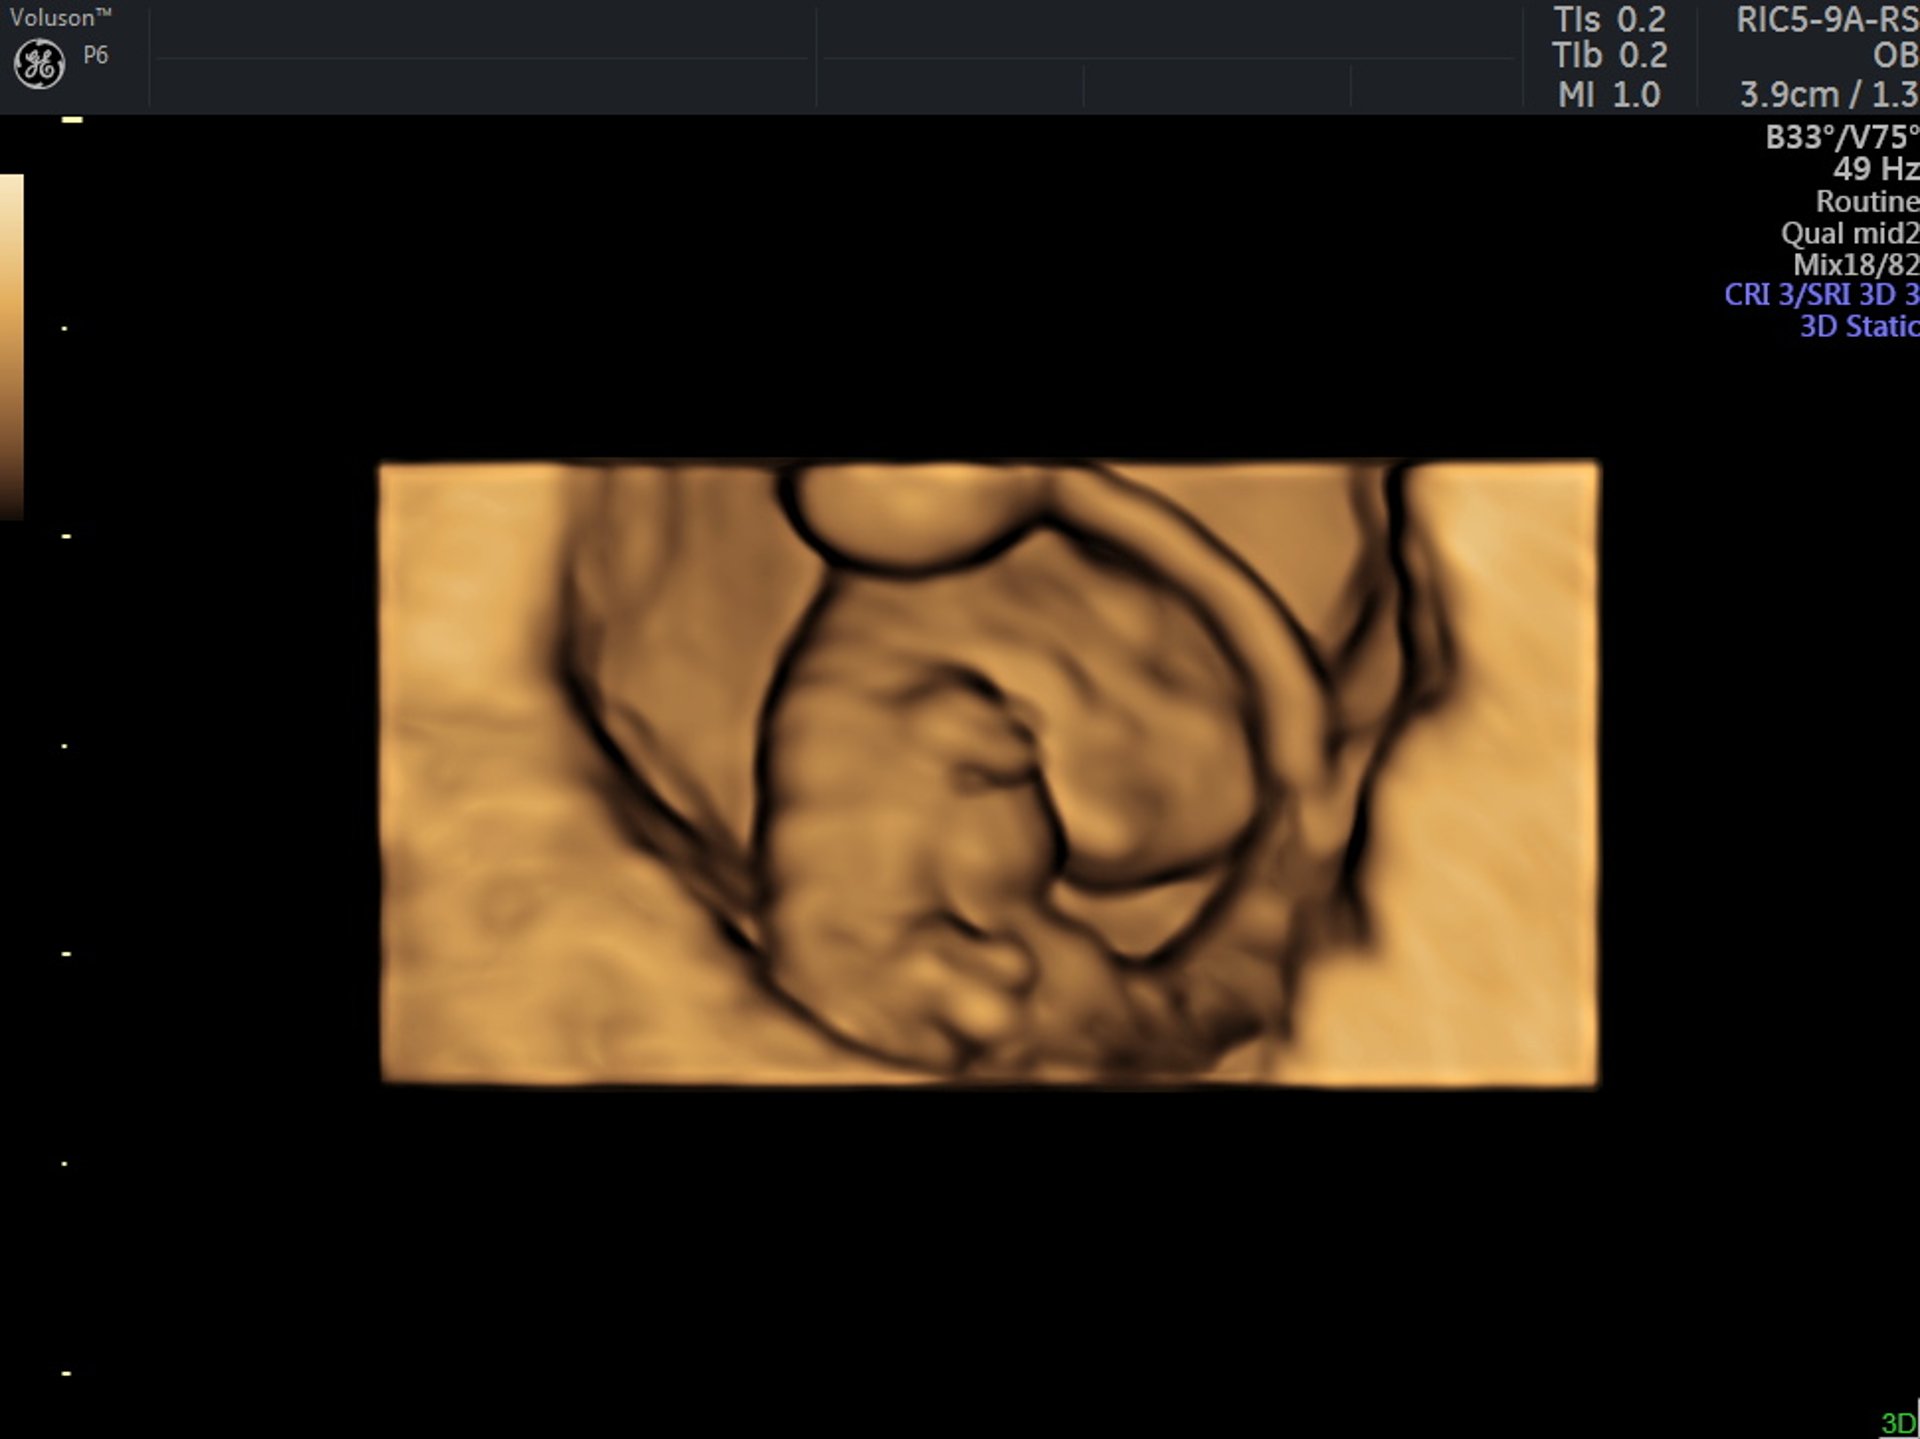

Várandósgondozás